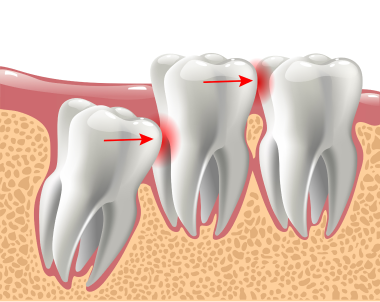

最後に生えてくる奥歯で狭い場所に生えるためほとんどが斜めや真横に生えてきます。同様の状態で歯茎の中にあり表面に出てこない場合(埋伏智歯・水平埋伏智歯)も多くあります。

3. 前の歯に影響を及ぼす可能性がある場合

狭いところに生えてきた親知らずはほとんどの場合、斜めや横に生えてきます。

そのため、前の歯を押しだし歯並びやかみ合わせに影響が出る場合があります。

歯茎の中に埋もれた親知らずも同様に影響します。